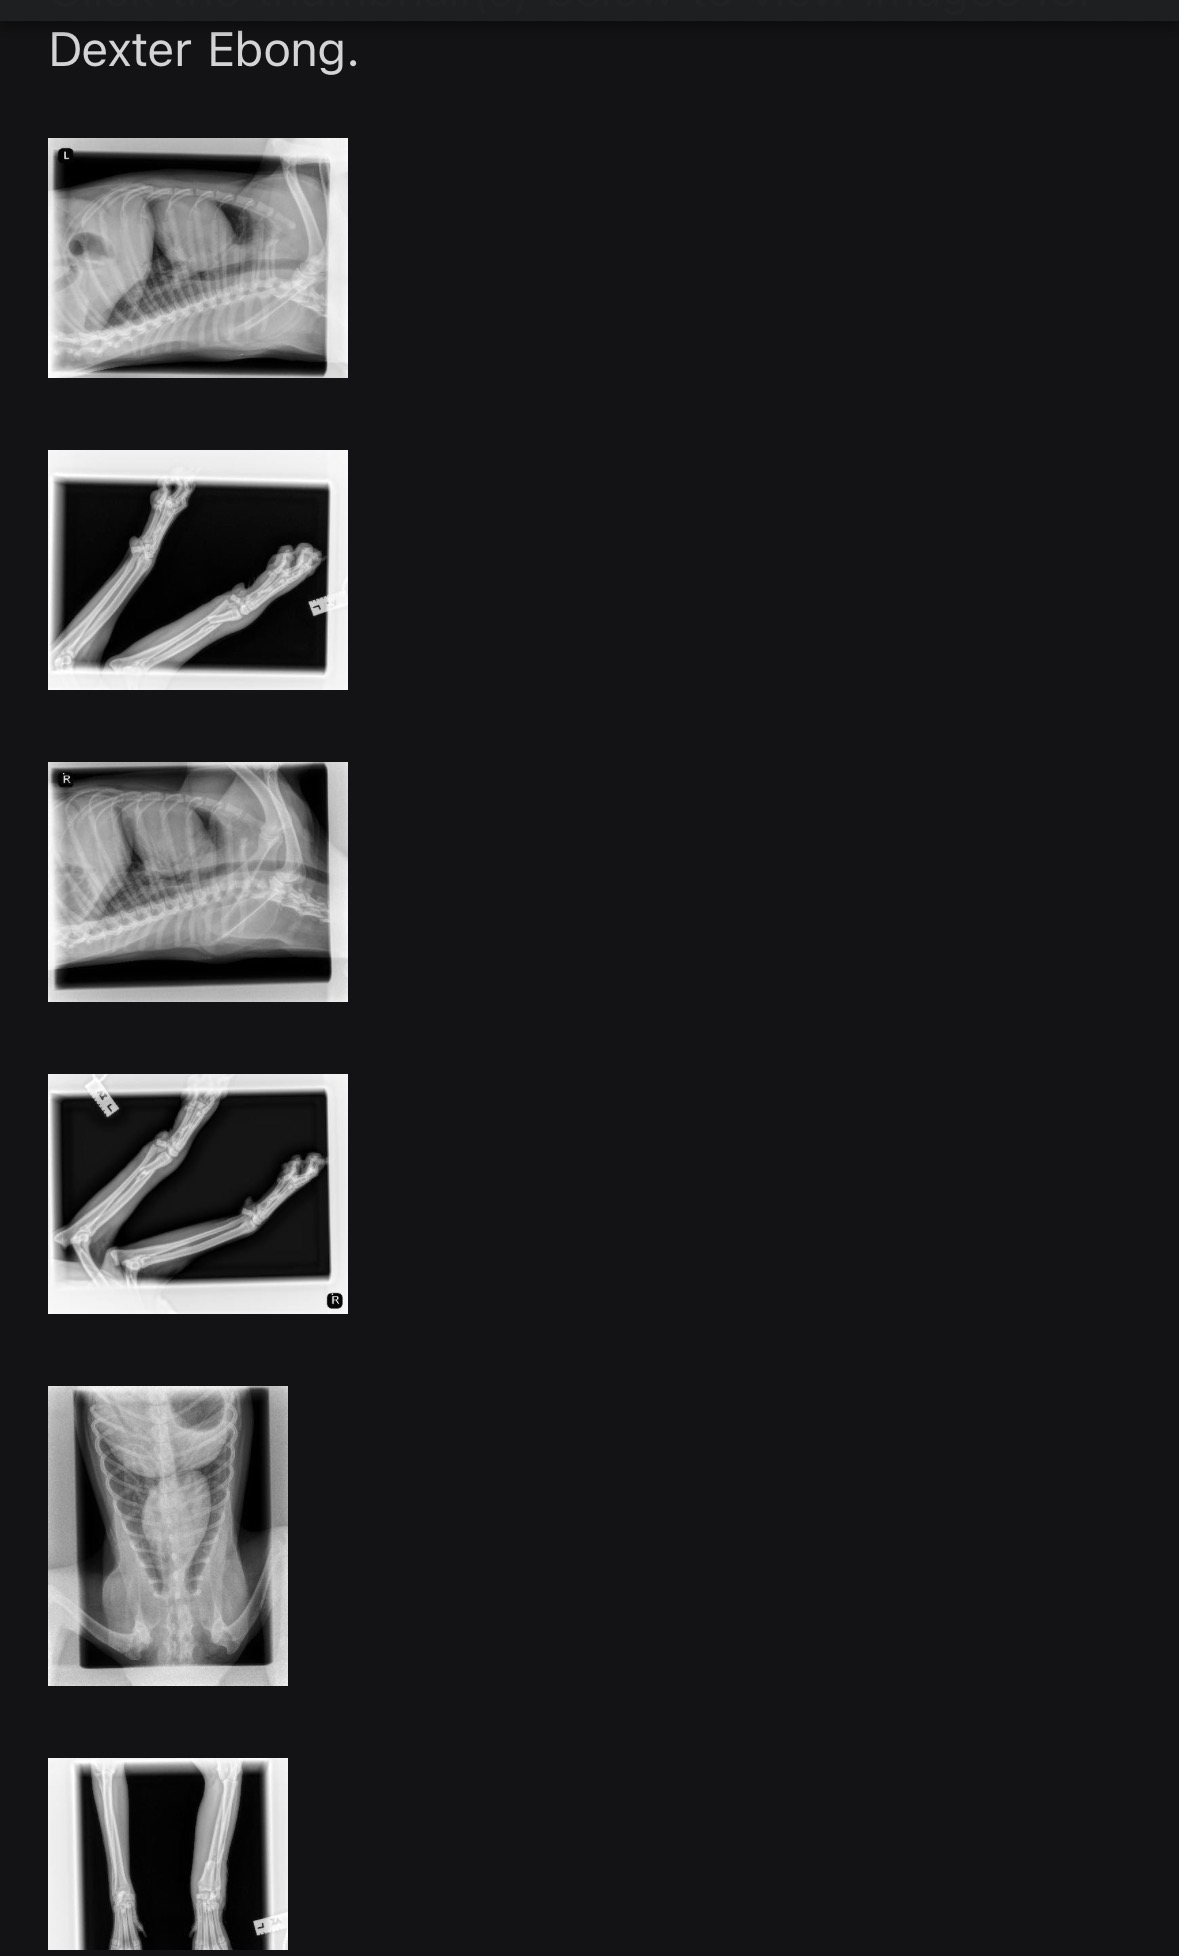

Hi Friends, I have some sad news about Dexter. He wiggled out of his harness one morning last week and took off running and ran smack dab into a parked car and fractured his front leg. His new owners took him to the vet where they x-rayed him and put a cast on his leg. The couple does not have the funds to pay for medical attention, so I am going to transport him back to Carlsbad shelter where he will get proper medical attention.